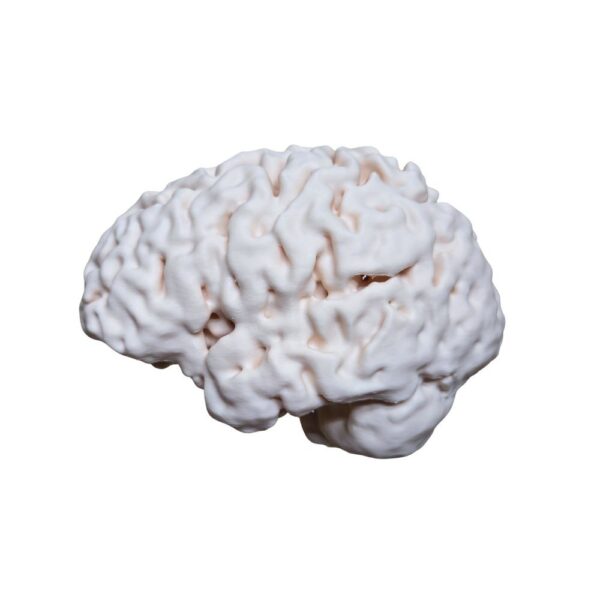

Obtenez une précision absolue avec cette réplique issue d’un scan 3D d’un véritable cerveau humain. Chaque circonvolution et structure est reproduite à l’identique de la réalité, offrant un outil d’étude et de référence d’un réalisme inégalé pour les passionnés et professionnels.

| Cerveau Humain Anatomique (Scan Réel) – Réplique Haute Fidélité | 1 11900 د.ج |